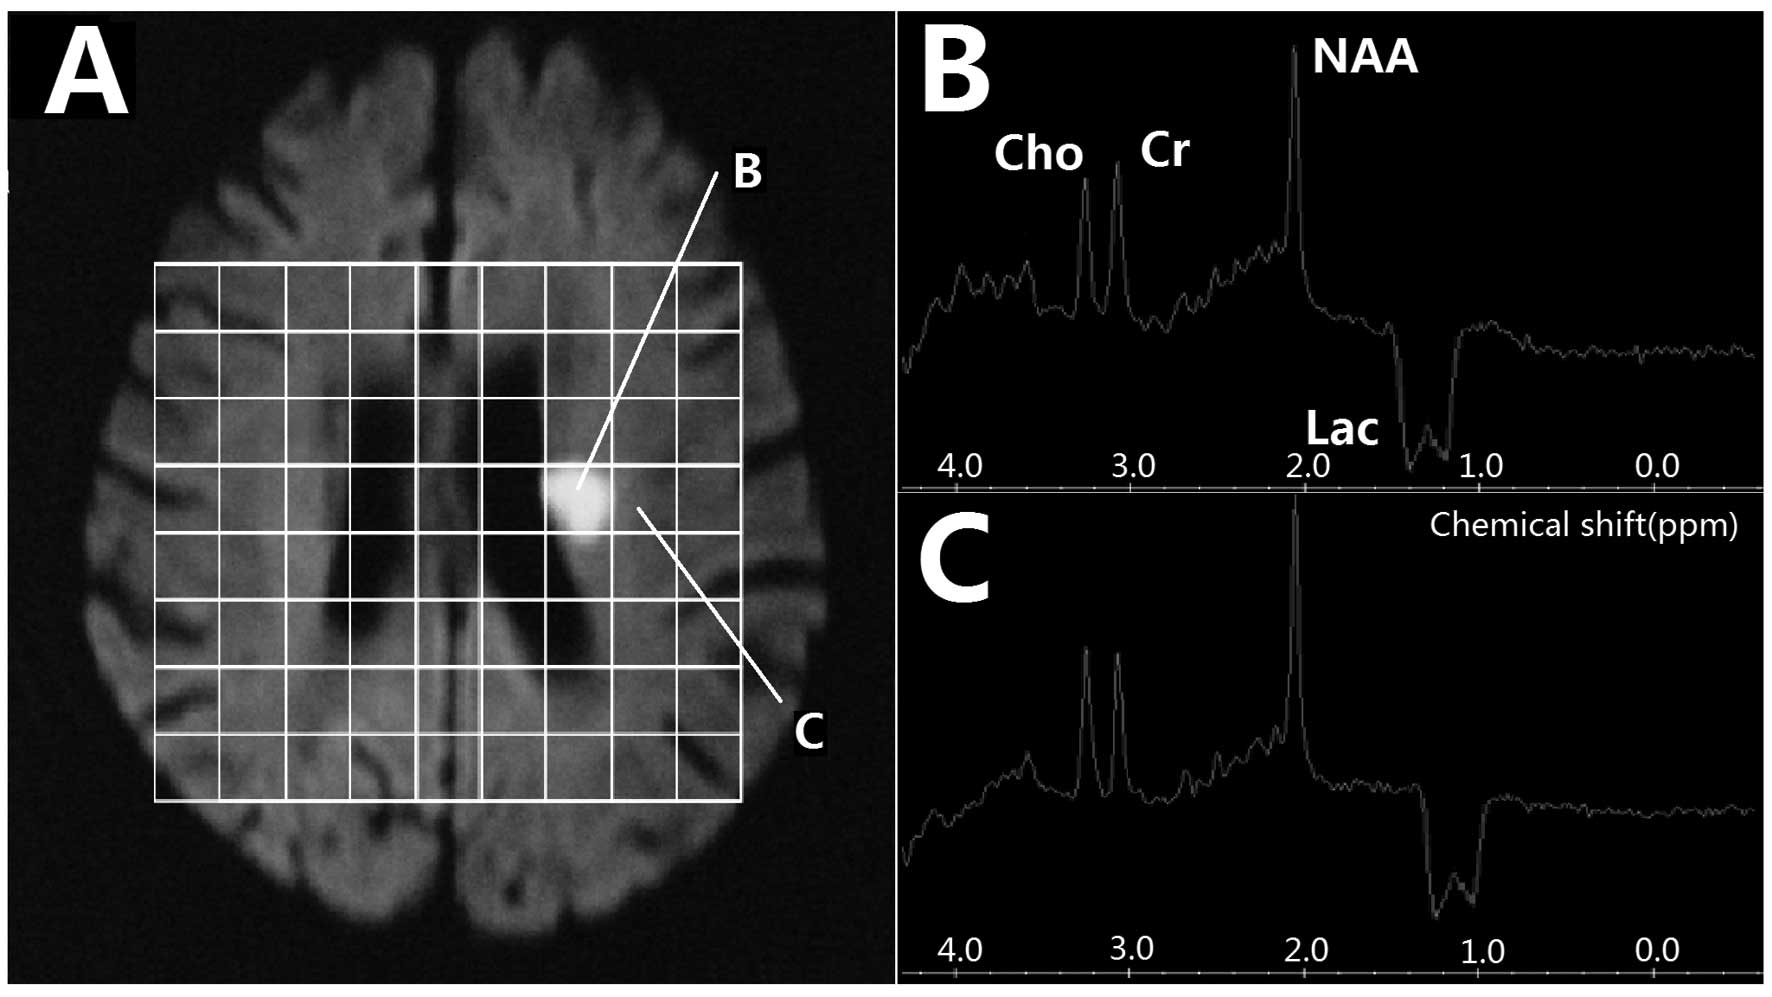

1H-MRS findings in the acute phase

All 72 lesions on 1H-MRS images showed a visible inverted Lac peak at 1.3 ppm, which included 52 bimodal and 20 single peaks. At the center of the lesion, NAA/Cho was significantly higher in the <6 h group than in the 6–12 h group, while the Lac/Cr was notably lower in the <6 h group than in the 6–12 h group (t=2.593, P=0.011; t=2.630, P=0.010; t=5.478, P<0.001, respectively). However, in the border region, the NAA/Cr and NAA/Cho ratios were only slightly decreased and an inverted Lac peak was present (Fig. 1 and Table I). Of the 47 patients, 21 (29 lesions) underwent the first 1H-MRS examination within 6 h after stroke and 26 (43 lesions) underwent 1H-MRS between 6–12 h afterwards. At the center of the lesion, NAA and Lac were decreased in the <6 h group compared with those in the 6–12 h group. However, the differences between the <6 h and 6–12 h groups were not statistically significant at the infarction border region. The comparison of MRS values in the central and border region of lesions at different time points are presented in Table II.

Figure 1

Proton magnetic resonance spectroscopy (1H-MRS) in acute stage. (A) MRS map; (B) MRS of infarction center; (C) MRS of border region.